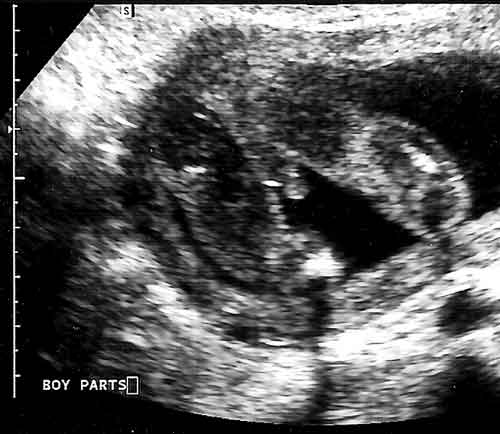

It's a Bob

January 26, 2007

Can we get a second opinion? How about a third? Really? Seriously? What the Hell are we going to do with a boy? Clara now feels justified calling it "Bob" even though we've told her again and again that when he comes out he won't be "Bob." "Will he be Mr. Wallace?" asked Clara. Yes. Too much White Christmas can be a bad thing. (Bob Wallace is Bing Crosby's character in White Christmas.)